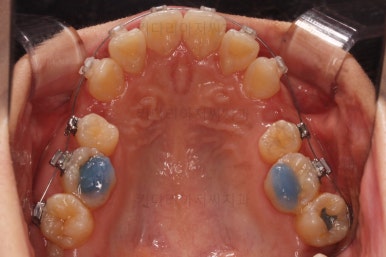

아래 앞니는 깊숙하게 솟구쳐 오른 치아를 밑으로 끌어내리기 위해 미니스크류를 식립하게 됩니다.

아랫니가 매우 밑으로 많이 내려온게 보이시죠?

과개교합은 비교적 초반에 개선이 되었습니다.

아래 앞니의 높이가 개선된 뒤, 아랫니도 가지런하게 해줍니다.

윗니도 어느새 치아를 뽑은 공간이 많이 줄었네요.